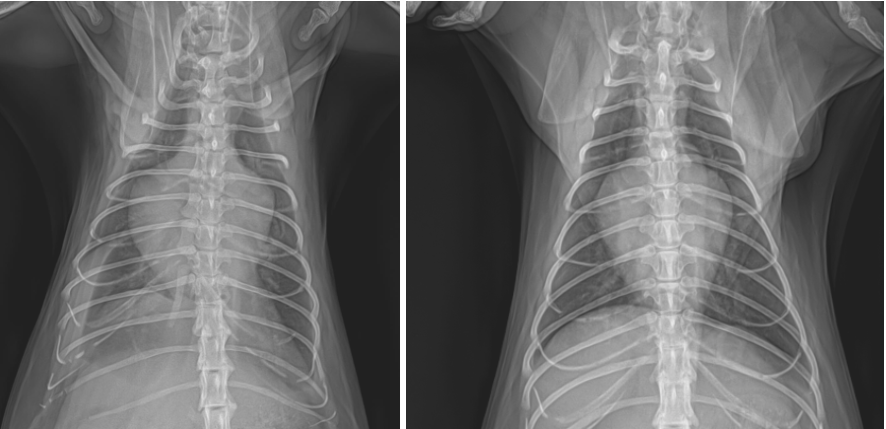

양산 고양이 제한성심근병증 내원 (좌) & 치료 후 (우) / 출처: 에스동물메디컬센터 양산점

1주일 뒤 재진에서 촬영한 X-ray에서는 심장 크기가 감소한 것을 확인하였습니다. 환자의 발열, 호흡 이상, 활력 저하 등의 증상 또한 모두 개선되었으며, 약물치료와 정기 모니터링을 통해 환자의 삶을 질을 개선하고 합병증 발생을 최대한 방지하도록 하였습니다.